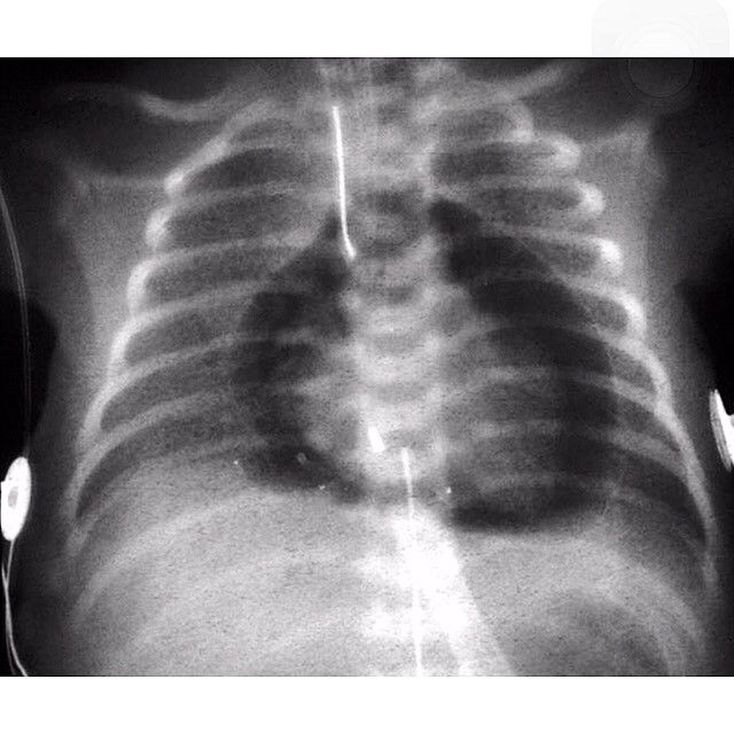

Chest radiograph shows air outlining the heart, a condition known as Pneumopericardium.The air is found within the pericardial cavity. In adults, it may be seen in the context with severe blunt chest trauma, pneumothorax, pneumoperitoneum, thoracic surgery / pericardial fluid drainage, or infectious peticarditis with gas-producing organisms.It's a serious complication, which if untreated may lead to cardiac tamponade and death. A pneumopericardium can be distinguished from pneumomediastinum, since air in the pericardial sac should not rise above the anatomic limits of the pericardial reflection on the proximal great vascular pedicle.